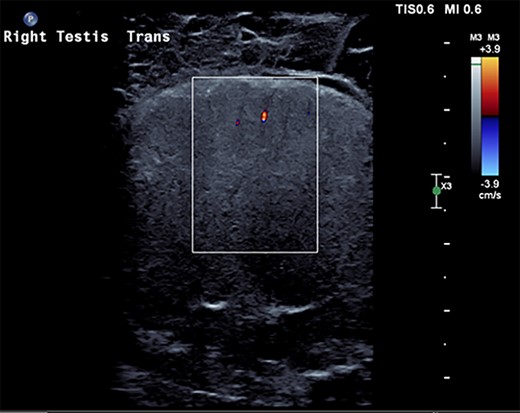

A 27-year-old male presented to the emergency department with acute scrotal pain for 48 hours. He has been having 1-week history of ongoing dull right testicular pain, was diagnosed with epididymal orchitis by his general practitioner and given a week of Augmentin Duo Forte (DF). He denied any history of cryptorchidism. He also has a large right inguinal hernia containing omentum that has been present for 1 year and was awaiting elective repair. Forty-eight hours prior to presentation, his 2-year-old, 20 kg son kicked him in the scrotum. He denied any abdominal pain, dysuria or hematuria. On examination, his right hemiscrotum was grossly swollen, with midline shift of the scrotum, a palpable inguinoscrotal hernia, erythematous, absent cremasteric reflex and a difficult to palpate right testicle. His left testicle had normal examination. He had an urgent scrotal ultrasound (US) showing reduced vascularity of the right testicle, query ischemia (Fig. 1). He then had a computed tomography abdomen and pelvis with contrast showing a large right indirect inguinal hernia containing fat (Fig. 2). On examination, his right hemiscrotum was grossly swollen, with midline shift of the scrotum (Fig. 3), a palpable inguinoscrotal hernia, his scrotum was erythematous, with an absent cremasteric reflex, and a difficult to palpate right testicle. His left testicle had normal examination. He underwent a scrotal exploration with findings of sliding right inguinal hernia with large amount of very stuck and strangulated omentum. The right testicle was found to be infarcted, multiple stabs of the testicle revealed no perfusion, turbid fluid was also noted and the head of the epididymis was necrotic (Fig. 4).

US scrotum showing lack of arterial blood flow to right testicle.